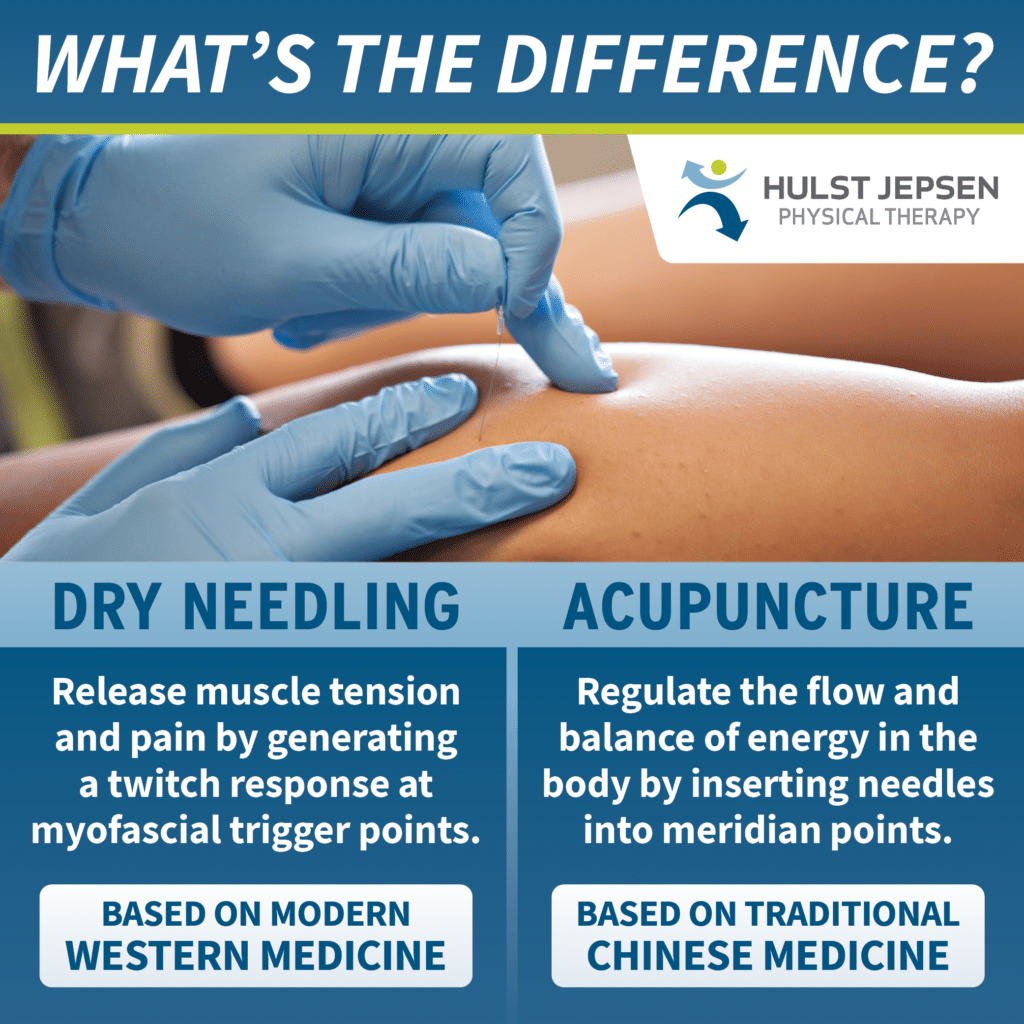

Dry needling – Isn’t that like acupuncture?

Dry Needling | Hulst Jepsen

Dry Needling vs Acupuncture: Pros and Cons | Lindy Health

What is dry needling? Isn’t it just acupuncture? – Jade Acupuncture and …